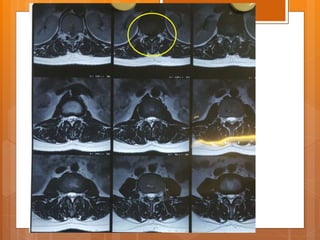

Case presentation  Female 21 y/o  Back pain from 1.5 years ago  Exacerbated after child delivery (9m ago)  Pain radiated to right leg from 7m ago

P/E  ↓L3 ,L4 force  right clonus  ↓ achilles DTR  QC DTR normal  Babinski sign normal  Intermittent Bladder dysfunction  Sensory normal